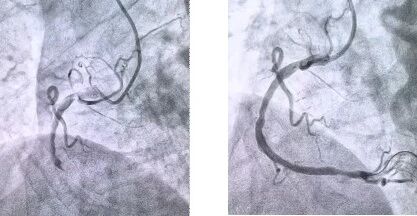

患者抵達(dá)醫(yī)院后,簡化掛號、繳費(fèi)等中間環(huán)節(jié),迅速溝通病情,需要緊急介入治療,獲得家屬同意,立即送至導(dǎo)管室。造影顯示其右冠狀動脈中段完全閉塞,醫(yī)生迅速實(shí)施血栓抽吸,球囊擴(kuò)張和藥物洗脫支架植入術(shù)。36 分鐘后,閉塞血管恢復(fù)正常血流,吳大爺?shù)难獕?、心率逐漸平穩(wěn),胸痛癥狀明顯緩解。術(shù)后三天,他便轉(zhuǎn)入普通病房進(jìn)行康復(fù)訓(xùn)練,重拾健康生活。